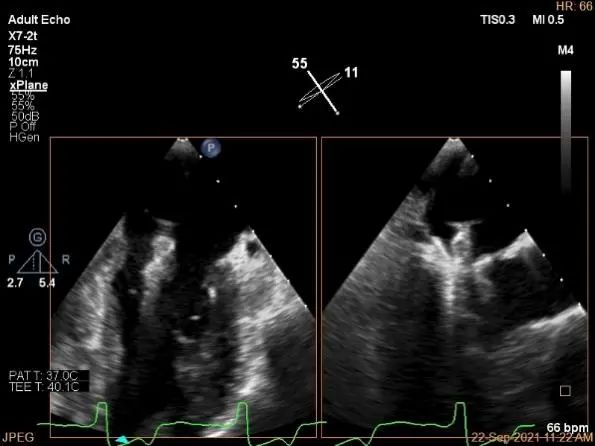

术中超声

P2区脱垂,宽14.8mm,Gap:3.3mm

3D-color,返流重度,3+级

麻醉状态下左肺静脉血流频谱

MVA:6.67cm²

房间隔穿刺点选择

穿刺高度:4.3cm